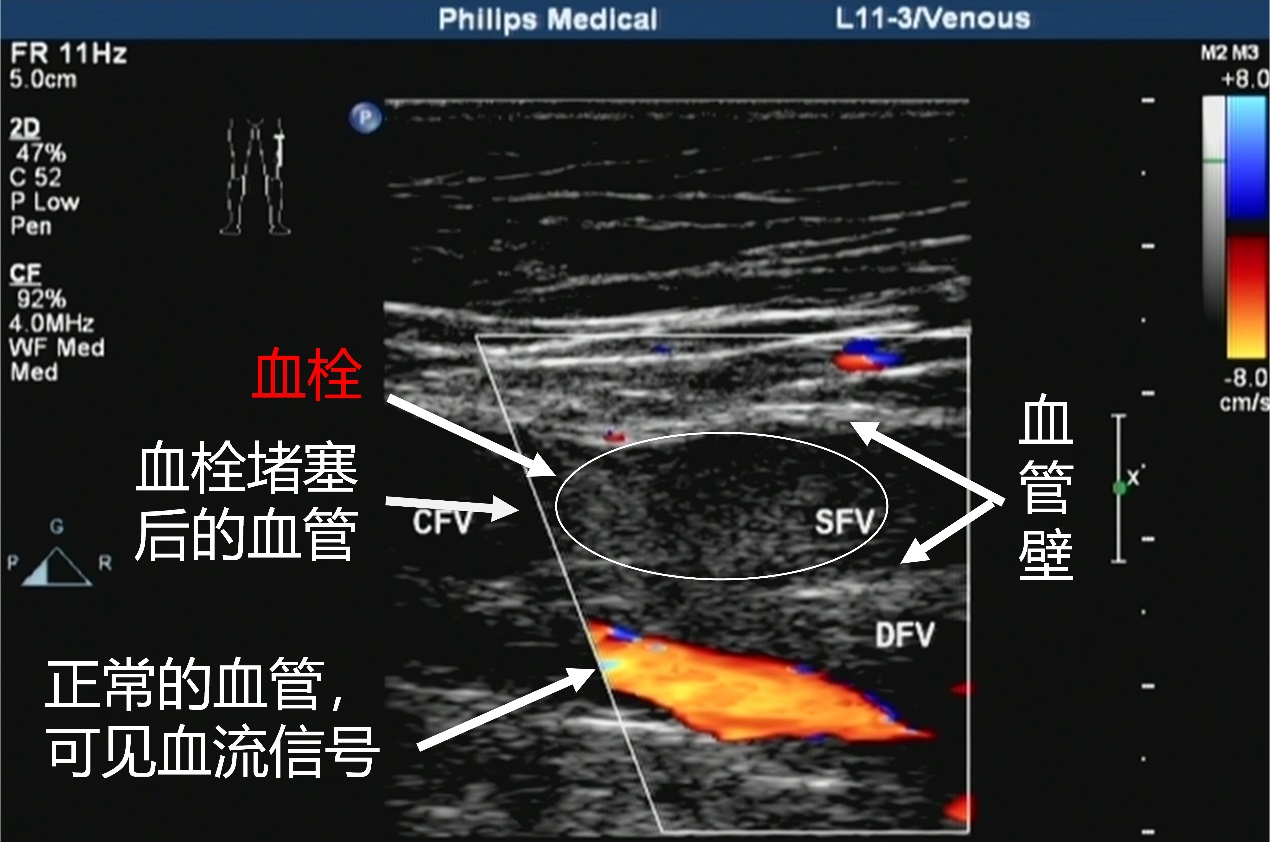

对于一个肿瘤患者,出现一侧肢体肿胀疼痛,活动障碍,不难诊断,B超一查,果然是下肢的深静脉血栓。这深静脉血栓不动还好,要是脱落了,那可就变成了栓子,随着血流跑,跑到肺部会造成肺栓塞,也就是肺梗死,出现胸痛、胸闷、咯血、呼吸困难等症状,严重的话可是要命的急症,我赶紧让患者卧床休息,减少下肢活动,使用抗凝药物,2个星期过后,老刘的左下肢明显好转,复查B超,血栓明显缩小了,血管也再通了,老刘悬着的心有放下了。